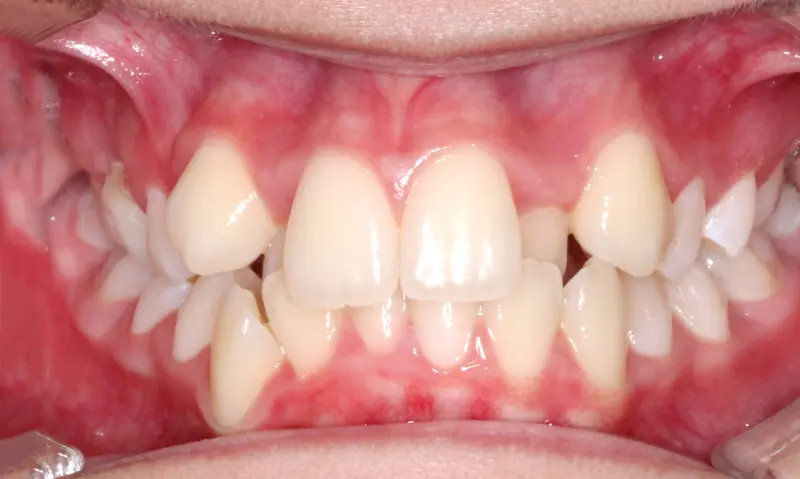

Phase 1 Early Intervention 10 Months

Unblocking Eruption Pathways

The Diagnosis

Severe maxillary constriction leading to blocked-out upper lateral incisors. The narrow dental arch lacked the necessary physical space for the incoming permanent teeth to erupt naturally.

The Engineering

Through targeted early intervention, we expanded the upper jaw to develop proper arch width. This crucial space creation unlocked the trapped lateral incisors, allowing them to safely enter the arch and establishing a broader, healthier foundation for the remaining adult teeth.

Instrument: Phase 1 Appliance Therapy

Before treatment: Unblocking Eruption Pathways

Before